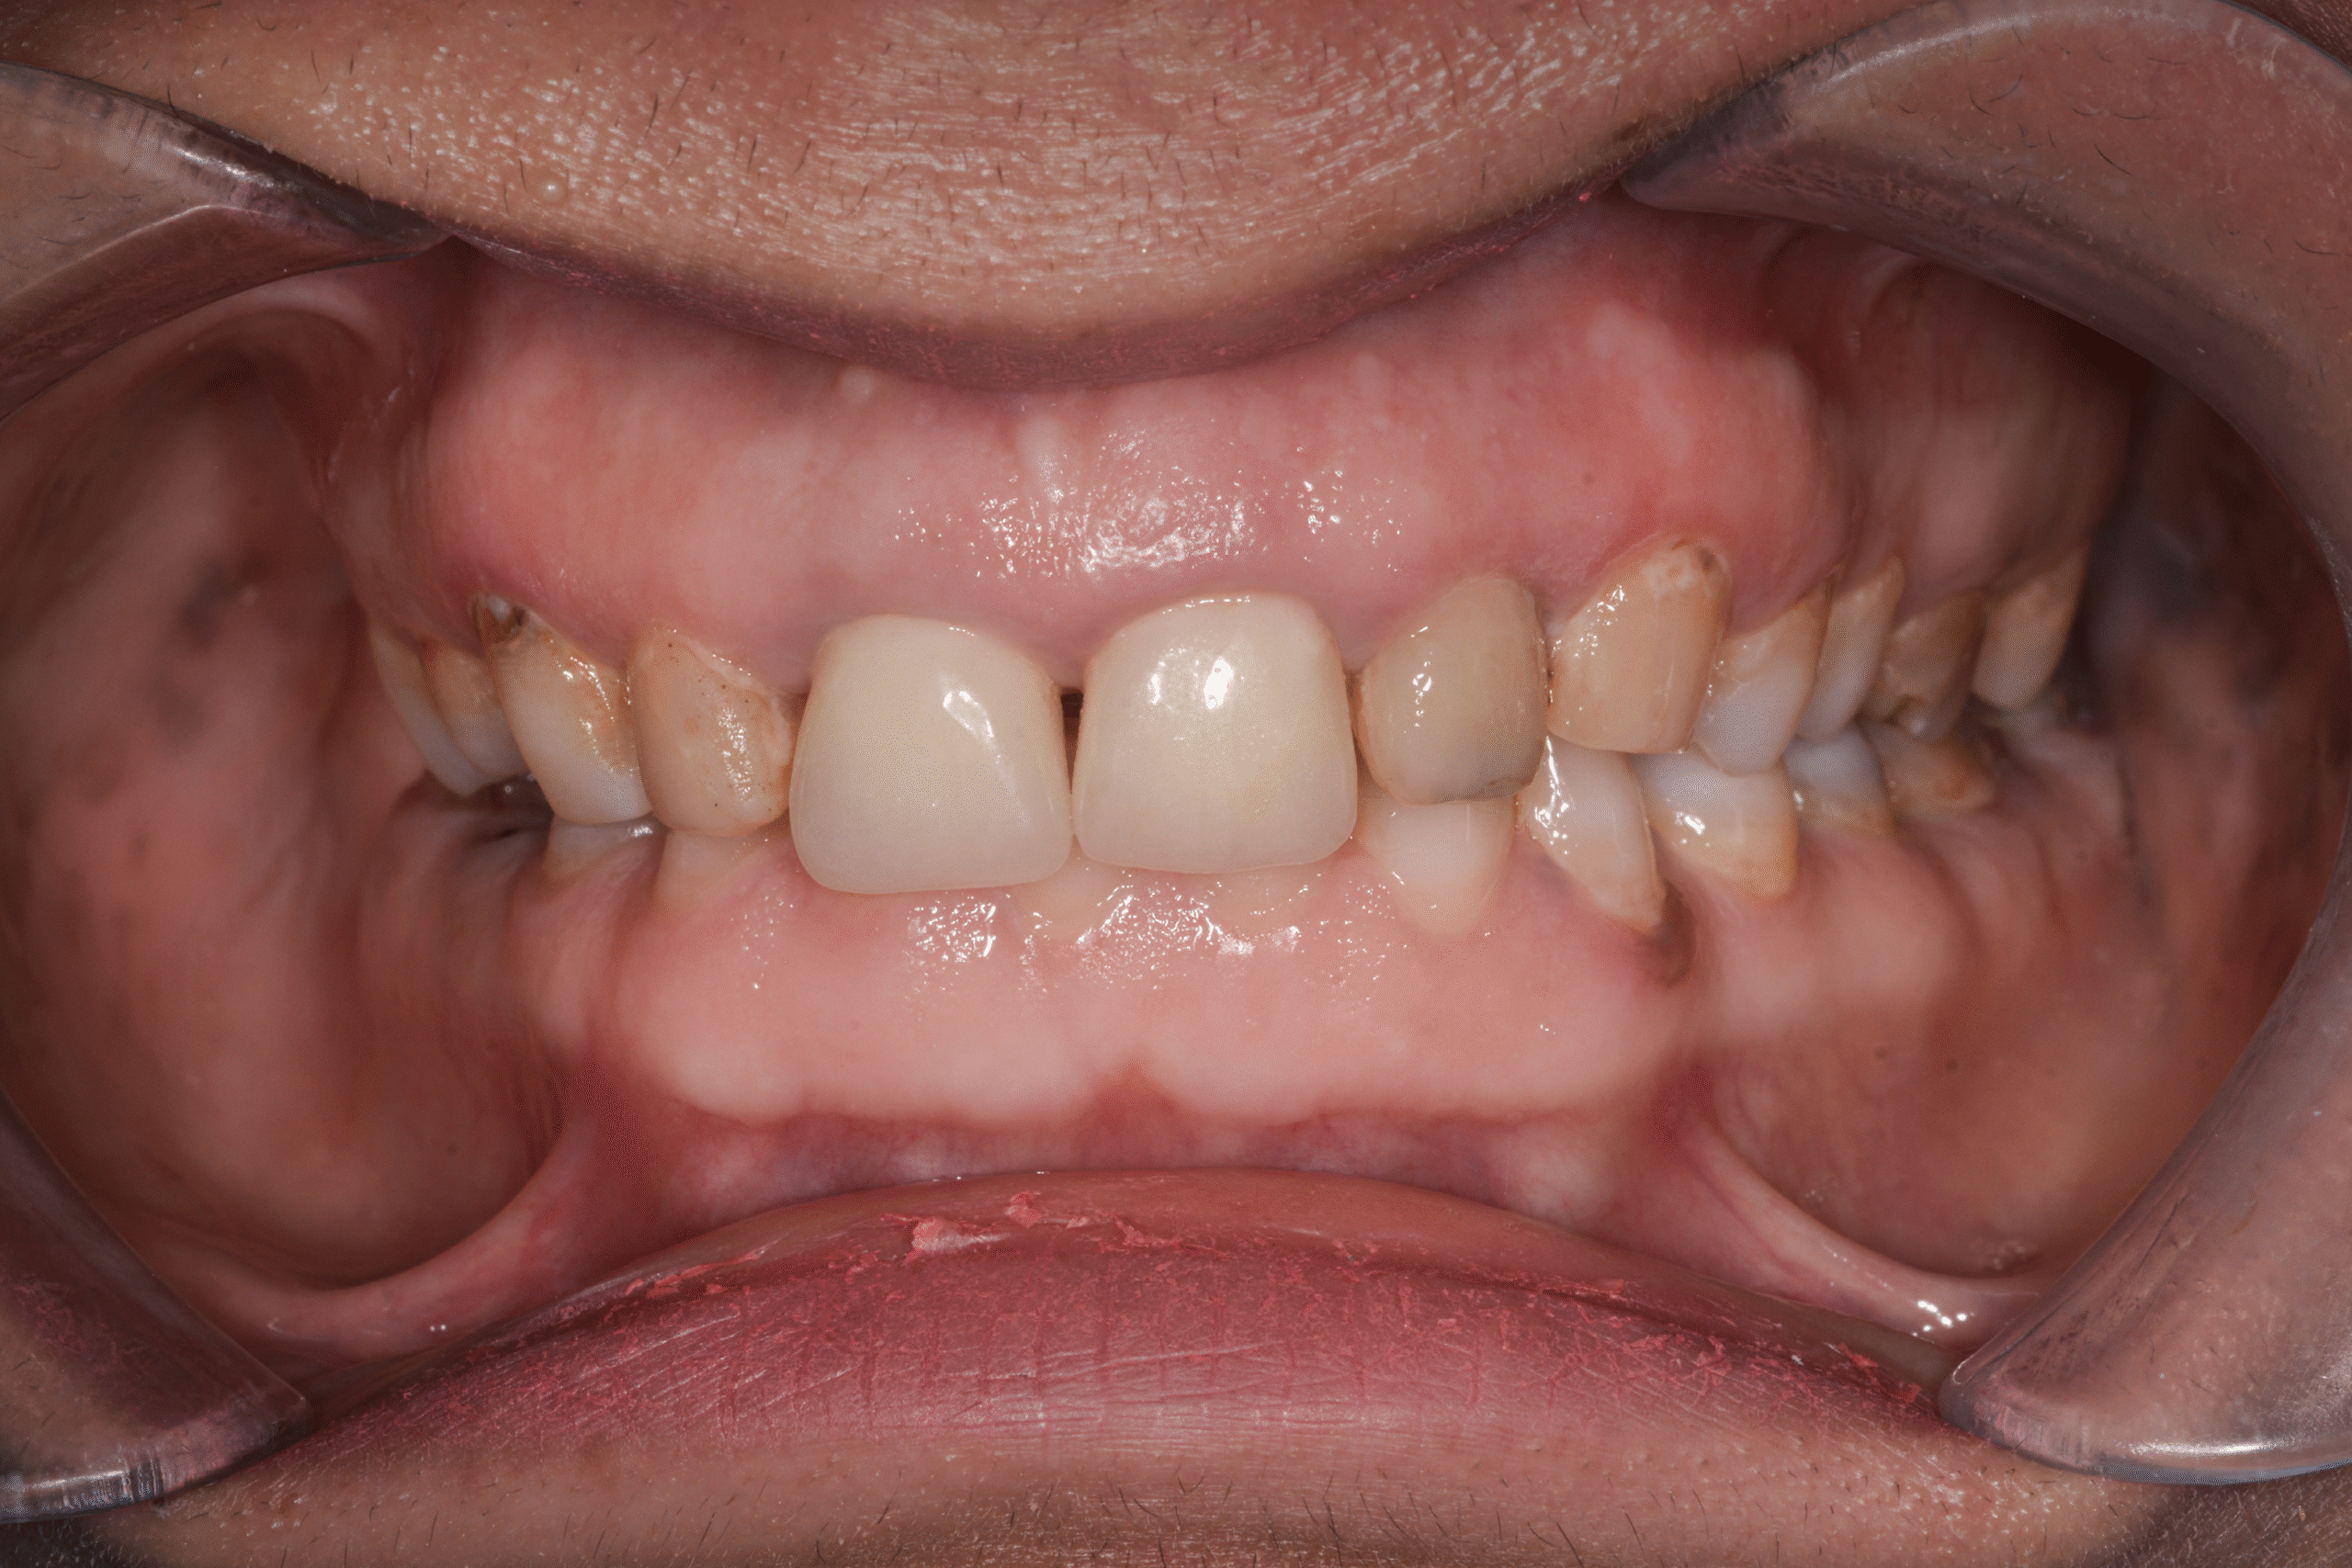

After

Emily’s treatment resulted in a fully restored, balanced bite and a renewed smile.

Her results included:

- Strong posterior support through implants

- Stabilized anterior teeth

- Corrected deep bite and improved chewing function

- Natural, aesthetic ceramic crowns

- Enhanced facial proportions and smile confidence

This case highlights how a carefully integrated approach—combining implant dentistry with ceramic restorative work—can successfully rehabilitate complex bite issues and deliver stable, long-lasting results.